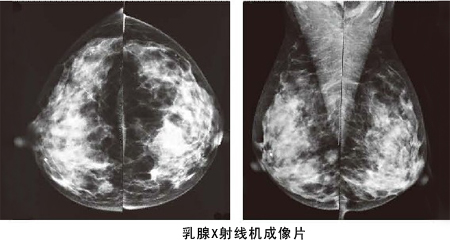

2、用專業(yè)影像設備來篩查乳腺癌

乳腺癌發(fā)現(xiàn)越早,治療效果越好。所以應該每年到體檢中心,做一次乳腺??茩z查,這是非常有必要的。建議25歲以后的女性定期乳腺檢查,35歲以上每年一次B超,40歲以后每1~2年進行一次鉬靶X線檢查。

鉬靶X線則是目前乳腺疾病檢查、發(fā)現(xiàn)和診斷早期乳腺癌的有效手段。BTX-9800A型鉬靶X線機采用現(xiàn)代科學技術(shù),自動化程度高,圖像清晰;人性化的設計使操作極為方便,成為乳腺疾病影像學診斷中的重要設備。